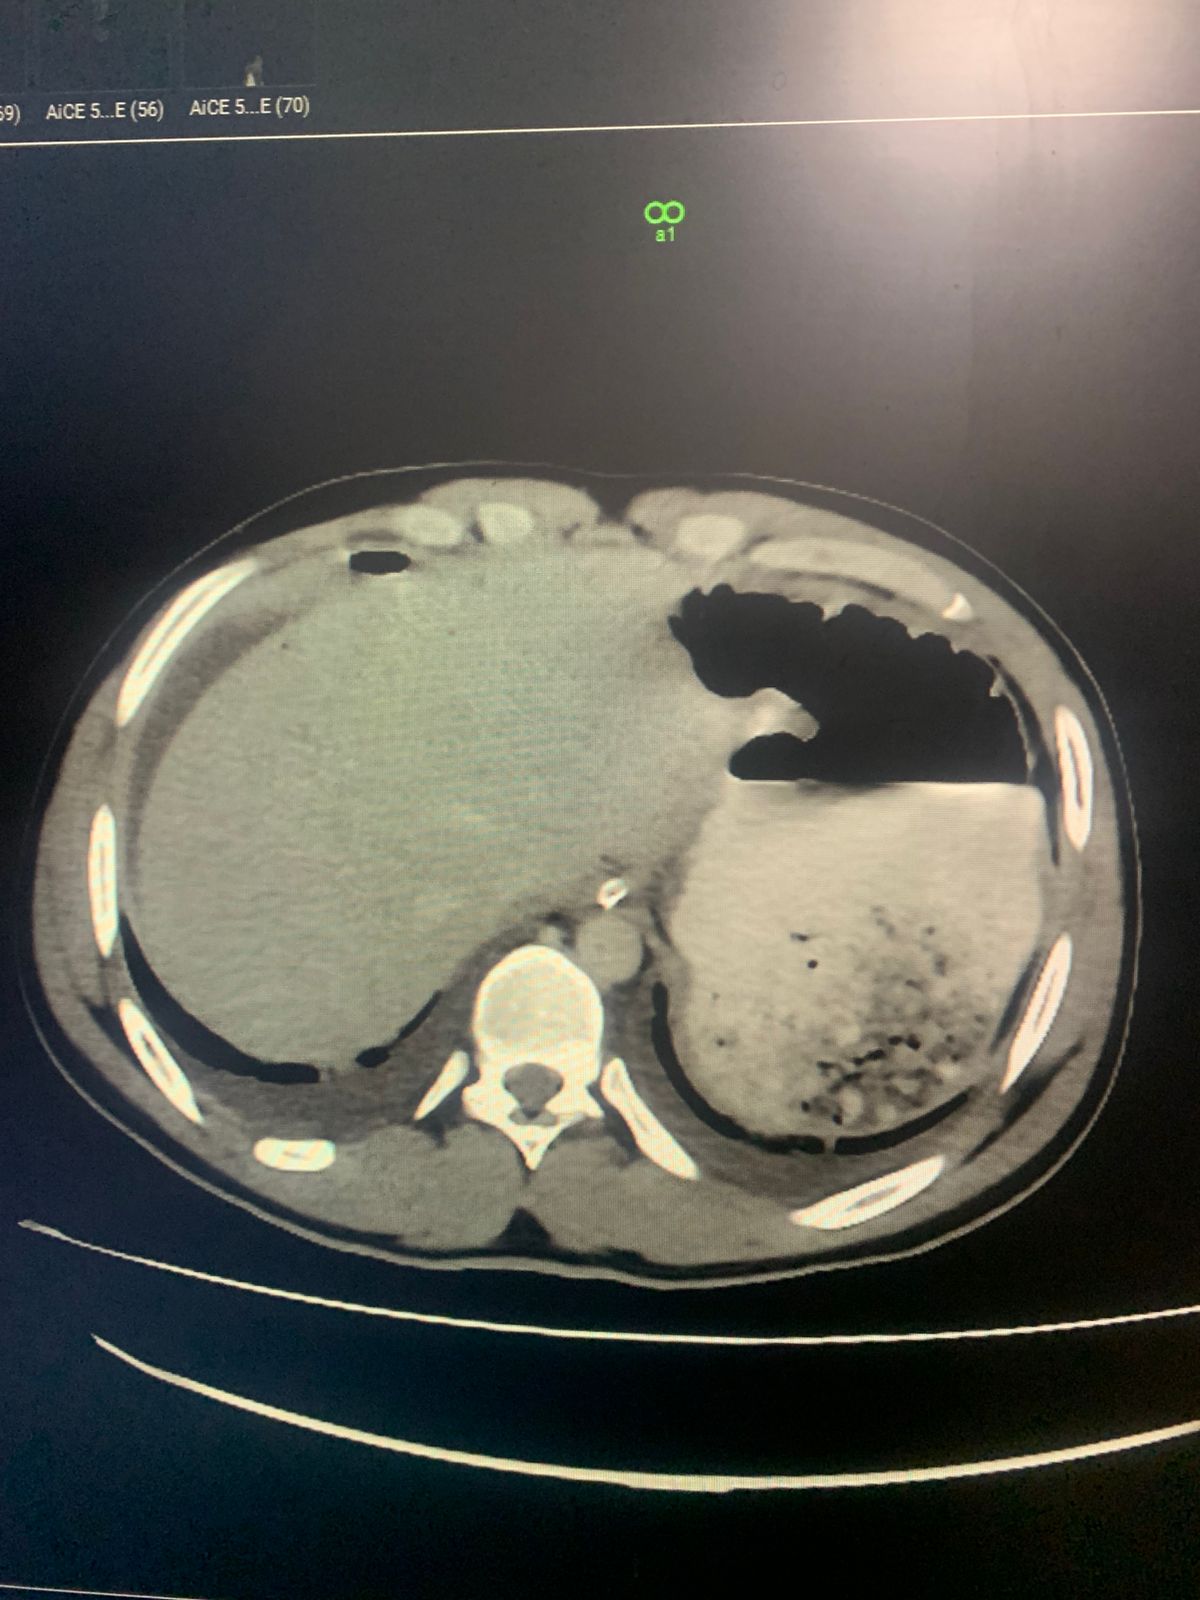

CT abdomen with IV and per rectal contrast

Findings :

. Bowel (sigmoid colon)perforation with leakage of contrast and Pneumoperitonium

. Moderate free fluid

. Portal venous gas

. Pseudoaneurysm of right external iliac artery

. Mild Bilateral pleural effusion